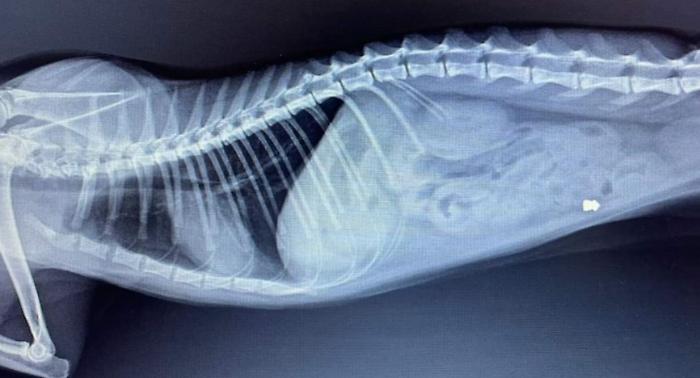

La radiografia di Oscar, colpito con una fucilata

"Chiunque abbia visto o sappia qualcosa si faccia avanti e denunci quanto accaduto contattando il numero 392.272.83.33". L'Ente nazionale protezione animali invita i cittadini a parlare qualora sappiano chi ha sparato ad Oscar, il gatto ferito con un colpo di carabina ad aria compressa a San Giustino Valdarno, in provincia di Arezzo. "Grazie all'amore della sua famiglia e alle cure veterinarie - scrive l'Enpa in una nota - Oscar sta lottando per riprendersi, ma l'indignazione per l’accaduto è enorme. La sezione locale dell’Enpa di San Giovanni Valdarno ha già sporto denuncia contro ignoti e invita" chi sa a farsi avanti. "È inaccettabile - si legge ancora - che nel 2024 episodi di violenza così efferata contro animali indifesi continuino a ripetersi".